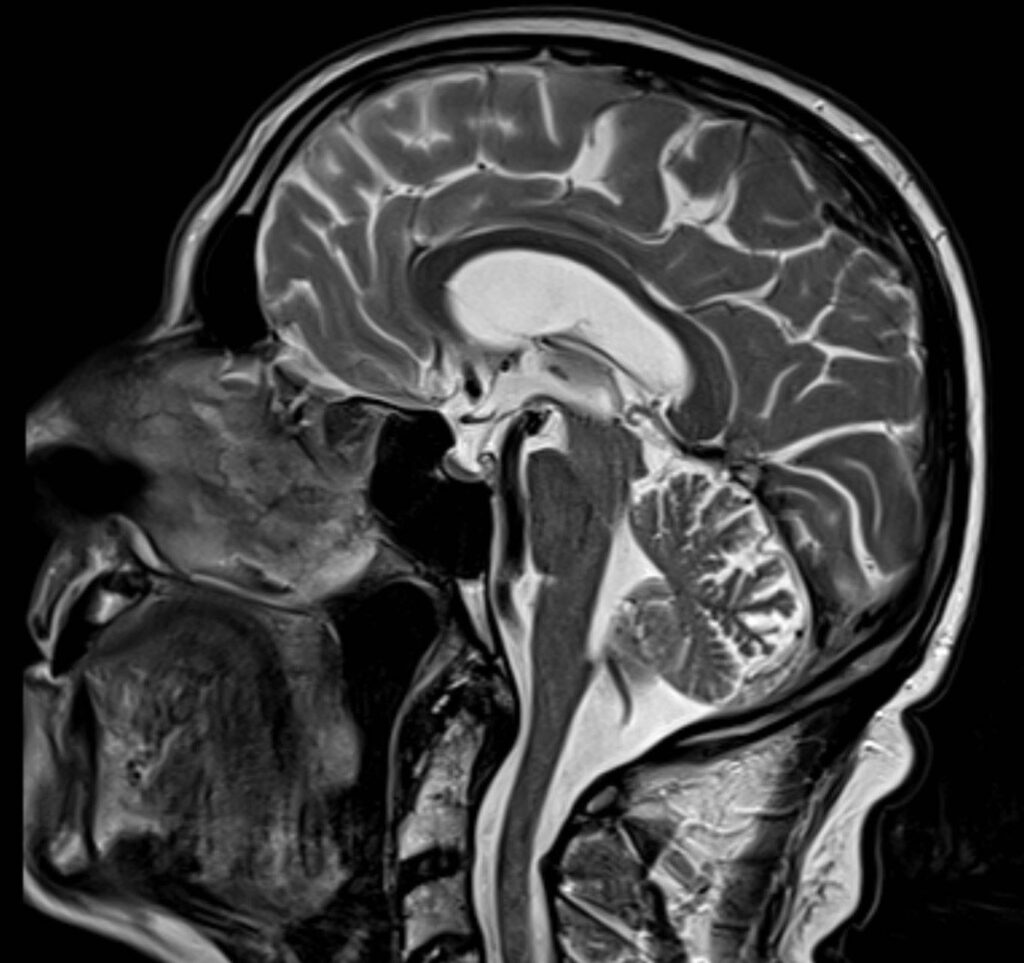

Eine Magnetresonanztomographie des Kopfes, kurz die MRT Kopf genannt, ist ein medizinisch bildgebendes Verfahren. Die MRT Kopf Untersuchung stellt mit Hilfe von Magnetfeldern und Radiowellen insbesondere unser Gehirn, Ohr, Nase und Nasennebenhöhlen, Augen, Kiefer, sowie genaue Strukturen detailliert dar. Vor allem bei diffusen oder langanhaltenden Kopfschmerzen kann eine MRT aufschlussreich sein. Vor allem ermöglicht eine Kopf MRT Einblicke in verschiedene neurologische Erkrankungen.

Eine Kopf MRT liefert Ärzte und Radiologen detaillierte Bilder. Zu sehen sind das Gehirn, Schädelknochen, Blutgefäße und anderer umgebende Gewebe im Kopfbereich.